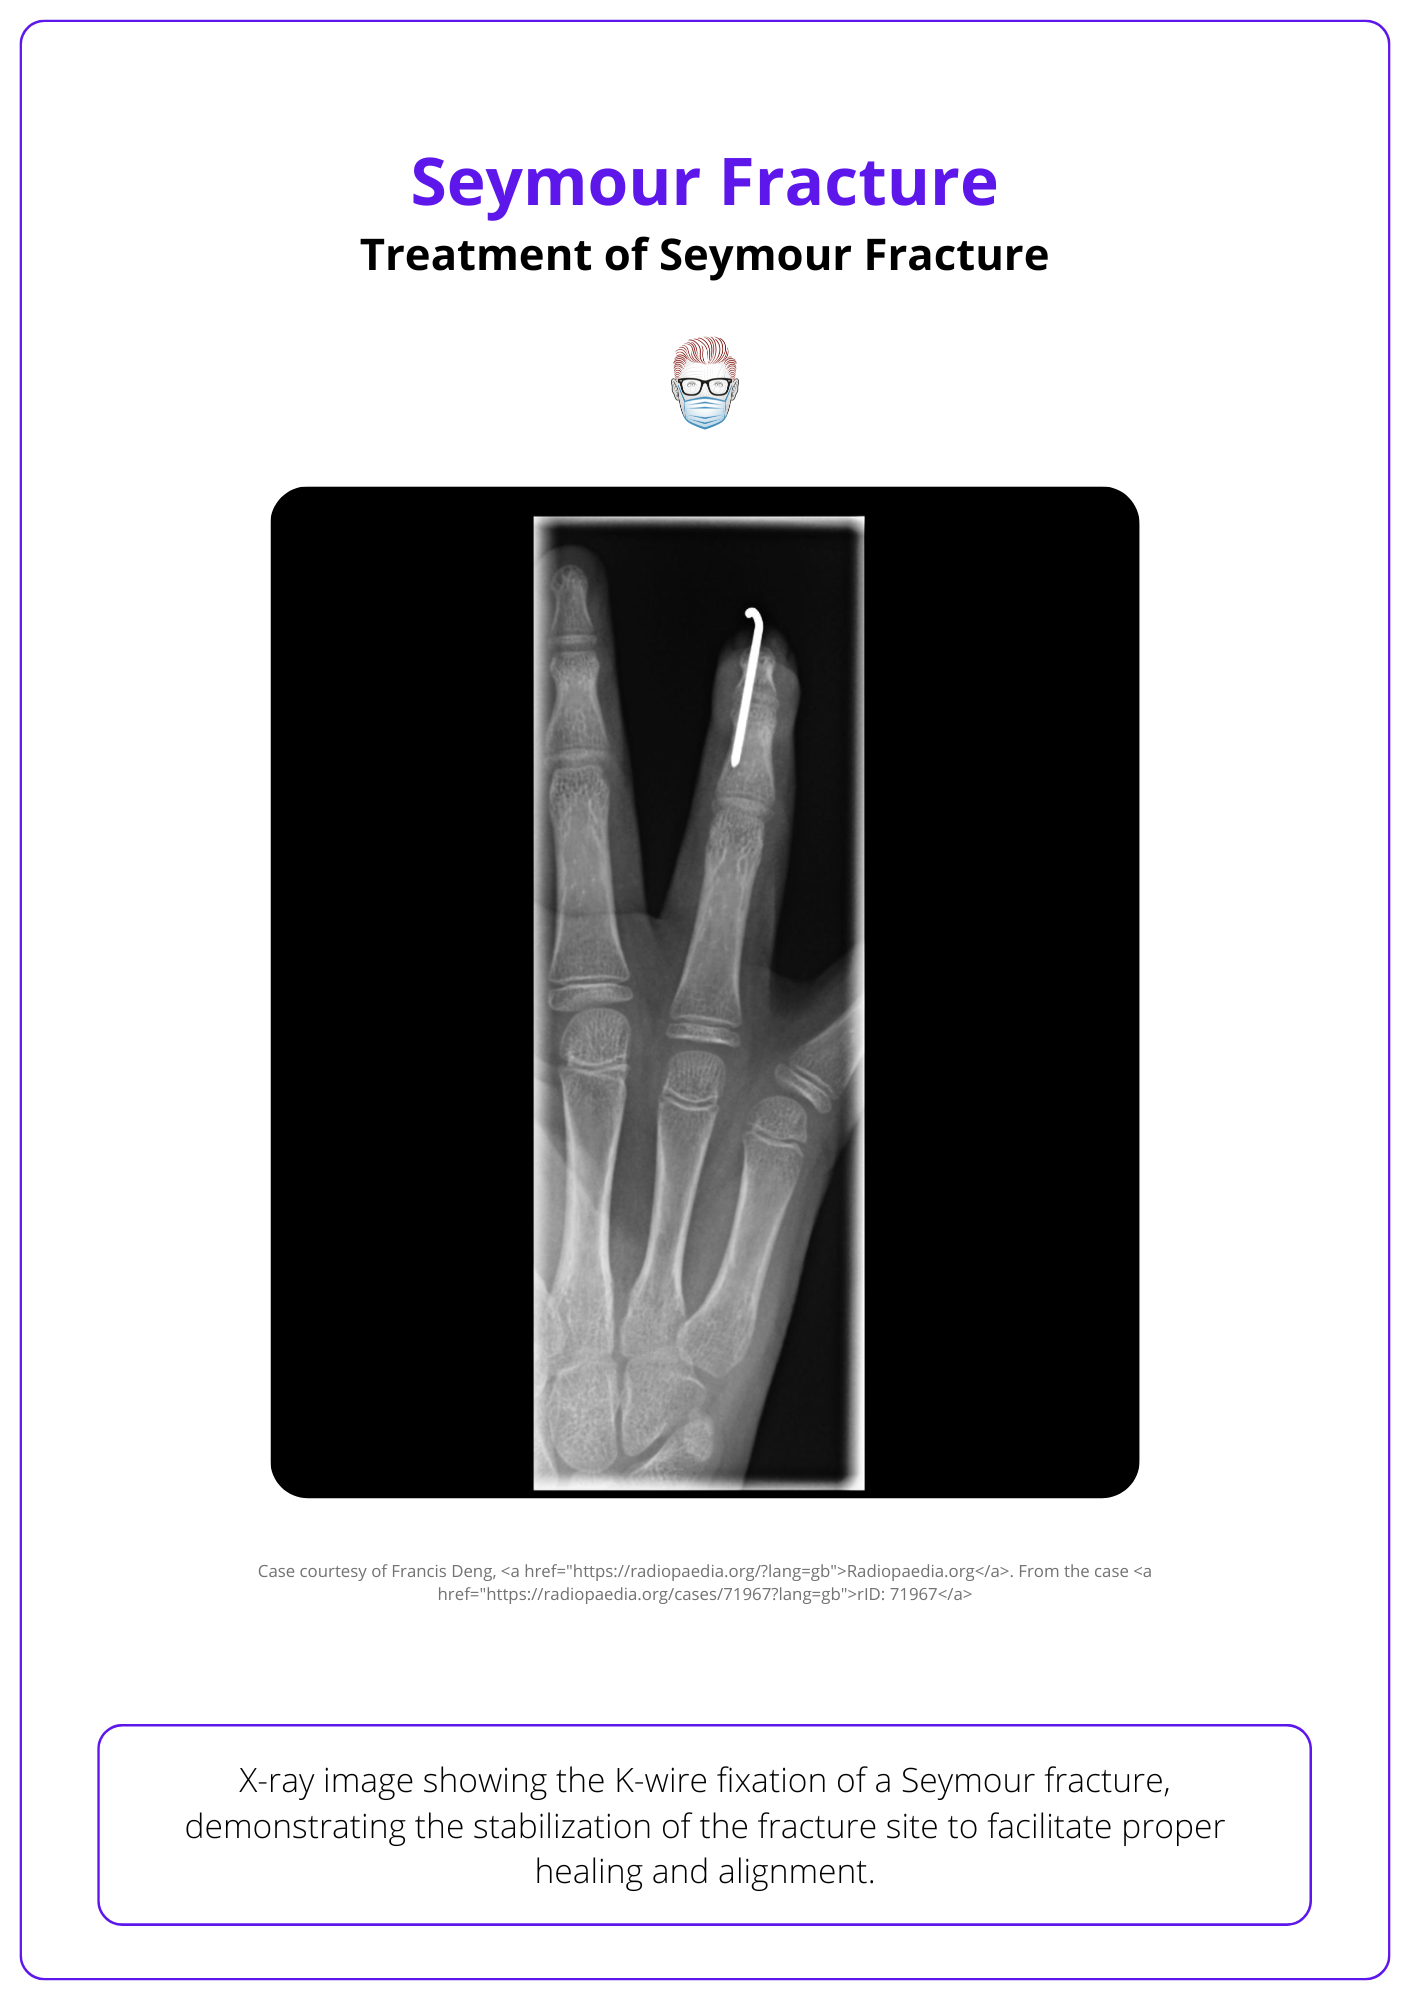

Treatment is multimodal and involves irrigation, debridement, reduction, fixation, and antibiotics (Krushe-Manndl, 2013). The recommended management of Seymour fractures can be looked at from both a soft tissue and bone perspective (Lin, 2019):

Fracture reduction.

- K-wire if the fracture is unstable or concern of patient non-compliance.

- Splinting the DIPJ if stable fracture after reduction and compliant patient.

- Tip: The nail aids in stable reduction by acting like a splint

The absence of fracture healing can be seen on radiographs - by trabecular bone or callus bridging across the fracture site (Samade, 2021).